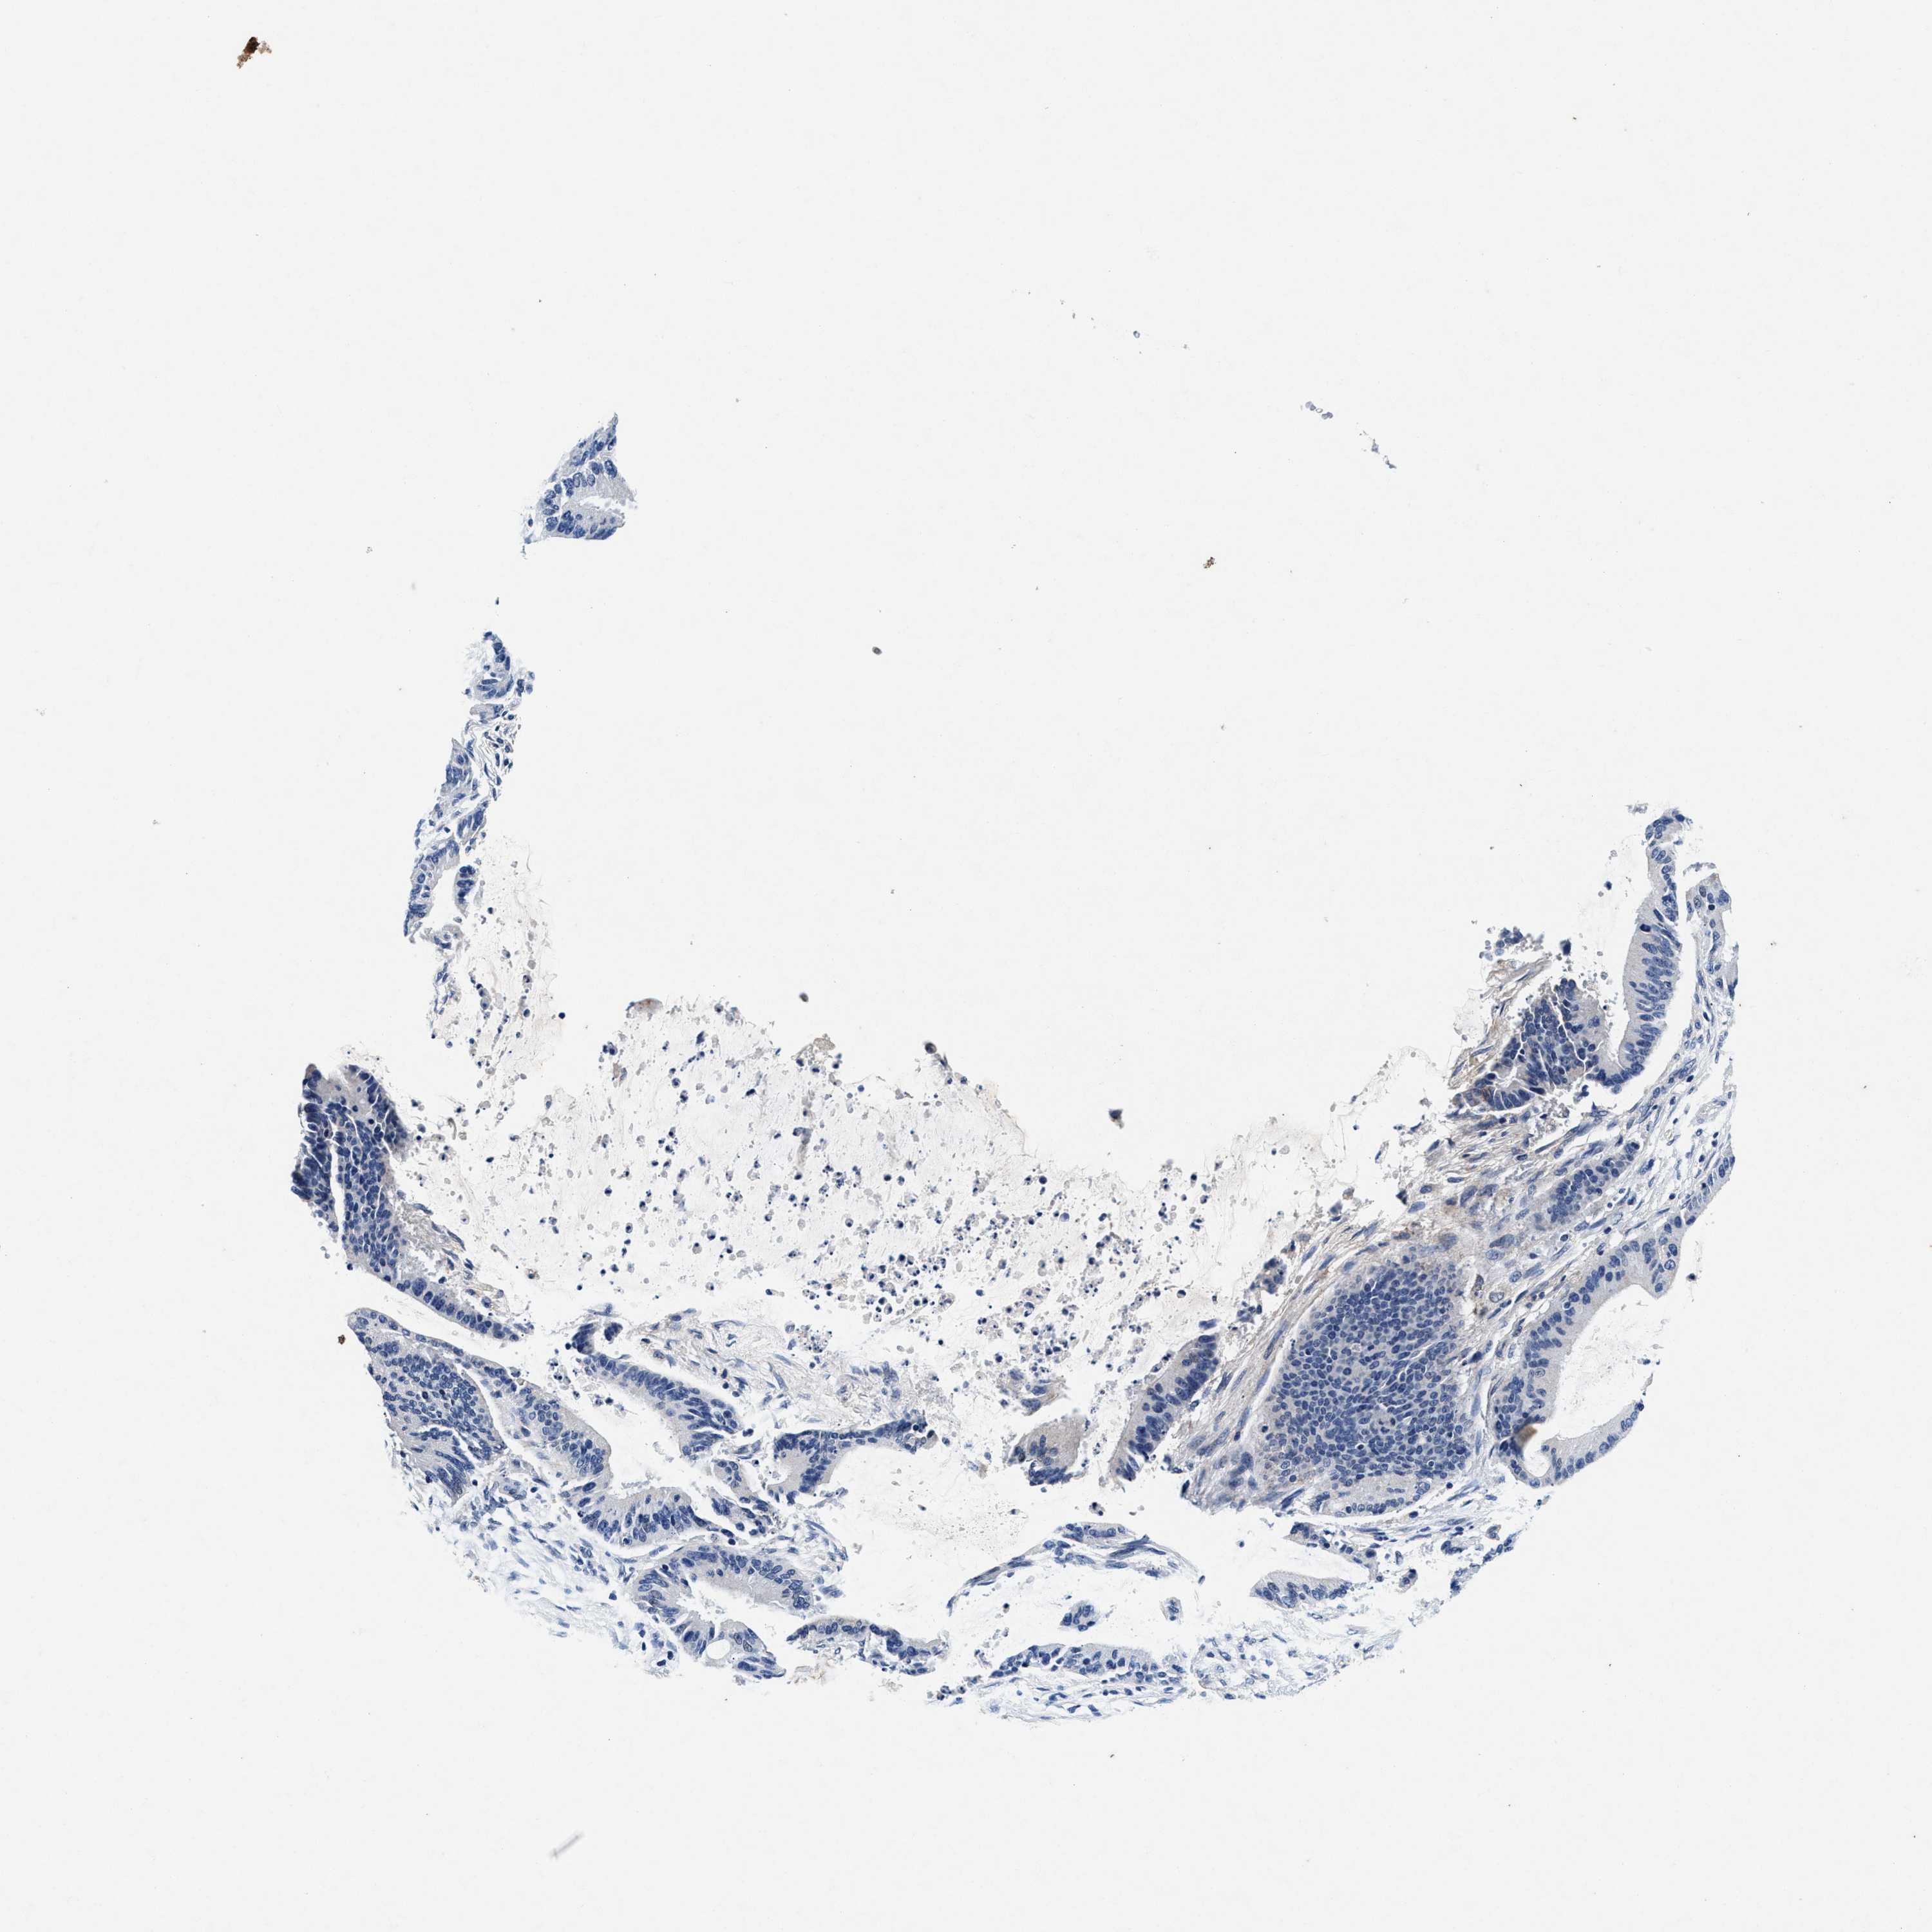

LIVER CANCER - Protein expressioni

A mouse-over function shows sample information and annotation data. Click on an image to view it in a full screen mode. Samples can be filtered based on level of antibody staining by selecting one or several of the following categories: high, medium, low and not detected. The assay and annotation is described here.

Note that samples used for immunohistochemistry by the Human Protein Atlas do not correspond to samples in the TCGA dataset.

Antibody stainingi

Antibody staining in the annotated cell types in the current human tissue is reported as not detected, low, medium, or high, based on conventional immunohistochemistry profiling in selected tissues. This score is based on the combination of the staining intensity and fraction of stained cells.

Each image is clickable and will lead to virtual microscopy that enables deeper exploration of all samples and also displays staining intensity scores, fraction scores and subcellular localization as well as patient and tissue information for each sample.

Antibody CAB022694

Staining

High

Medium

Low

Not detected

Intensity

Strong

Moderate

Weak

Negative

Quantity

>75%

75%-25%

<25%

None

Location

Nuclear

Cytoplasmic/membranous

Cytoplasmic/membranous,nuclear

Cholangiocarcinoma

Carcinoma, Hepatocellular, NOS